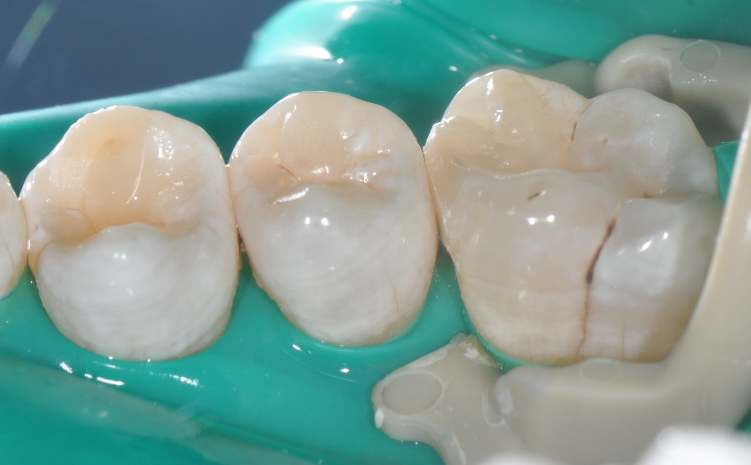

◆去腐完成之后

在以树脂充填为前提的案例中,无需过度制作颌面的鸠尾固位型,橡皮障下隔湿,是临床粘结操作技术成功的重要保障。酸蚀剂在使用的时候,需要尽量避免对邻牙的伤害